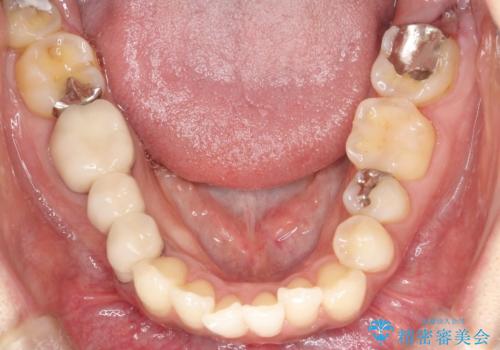

【インビザライン】矮小歯を有する方の矯正治療

- 前歯の凸凹を主訴に来院されました。

元々、歯が小さかったため矯正終了後にセラミックにて修復治療を行う治療計画をたてインビザラインにて治療を行いました。

今回はスペースを作るために歯列の拡大をメインでおこなっています。